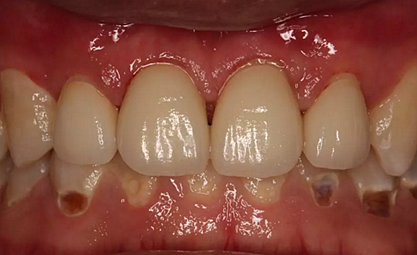

第5次復(fù)診的時候,終于讓我們4個兄弟恢復(fù)了正常的容顏。

現(xiàn)在剩下的任務(wù)就是為我其他的兄弟姐妹們治療了。需要做根管的做根管,需要做冠的做冠,需要樹脂充填的做樹脂充填。前前后后主人帶我們進(jìn)行了12次的復(fù)診,歷時6個月,現(xiàn)在的我們是這樣的

再來看看曾經(jīng)的我們

經(jīng)歷了如此長久的治療,主人應(yīng)該也是吸取了教訓(xùn),或許以后會改了不良的生活習(xí)慣,而我們經(jīng)歷了這段涅槃之旅,雖然也煥然一新,重塑了容顏,卻也是歷經(jīng)辛苦,如果主人能好好待我們,其實(shí)這樣的痛苦本不需要經(jīng)歷。